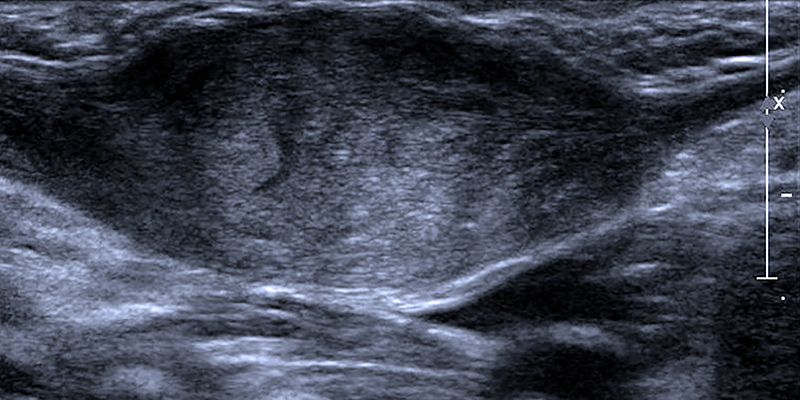

Een 2 weken oude baby komt vanwege een nieuw ontstane zwelling in de hals op het spoedspreekuur van de huisartsenpraktijk [figuur]. Haar moeder vertelt dat ze de zwelling 2 dagen geleden voor het eerst heeft gezien. ’s Nachts hoort ze ademstops. Er is geen sprake van koorts. De zwangerschap en partus verliepen ongecompliceerd. Bij lichamelijk onderzoek voelt de huisarts in de laterale hals een vaste, niet-mobiele zwelling van ongeveer 2 cm doorsnede. Het hoofd staat niet scheef en de ademhaling is hoorbaar. Diezelfde ochtend wordt een echo gemaakt waarop een verdikte musculus sternocleidomastoideus met een diameter van 1,7 cm te zien is, passend bij fibromatosis colli.

Bij twijfel is de diagnose eenvoudig te bevestigen met echografie. Dit is de gouden standaard en heeft bij deze afwijking een sensitiviteit van meer dan 95% en een specificiteit van 83%.911 De kenmerkende radiologische bevinding is een ovale of spoelvormige homogene massa binnen de musculus sternocleidomastoideus. Cysteuze en solide laesies zijn goed van elkaar te onderscheiden. Degene die de echo maakt kijkt naar mogelijk opgezette lymfeklieren en ingroei in omliggende structuren, waardoor fibromatosis colli en bijvoorbeeld een neoplasma van elkaar zijn te onderscheiden, hoewel deze laatste diagnose op deze leeftijd erg onwaarschijnlijk is.41012 Omdat het klinische beeld duidelijk te herkennen is en de aandoening met echografie makkelijk te achterhalen is, is het niet nodig om via een biopt weefsel te verkrijgen. Dit zou tot onnodige invasieve diagnostiek leiden, met alle risico’s en kosten van dien.